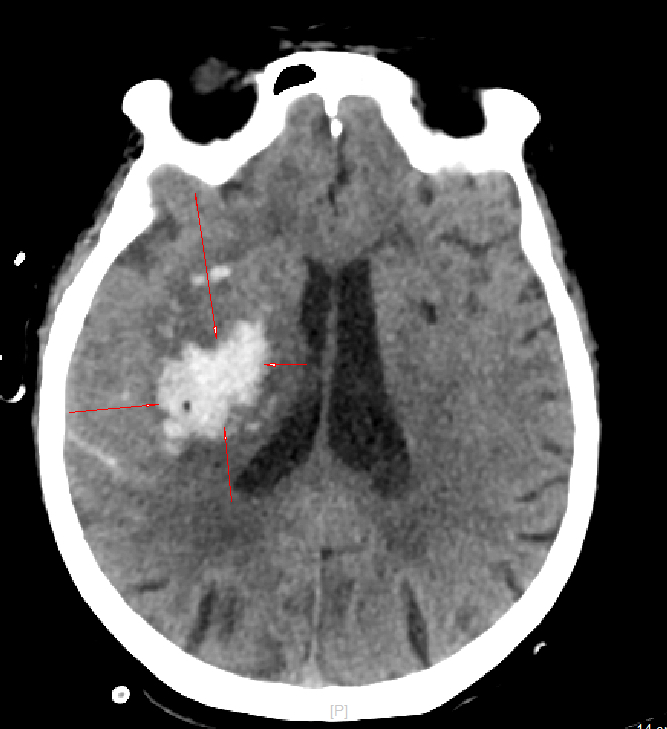

术后第一天CT

面对复杂病情,神经外科团队全面评估后认为,传统开颅手术创伤大、恢复慢,对高龄患者风险较高。而“硬通道穿刺引流术”具有创伤小、定位精准、手术时间短、恢复快等优势,更为适合。在充分沟通后,团队为患者紧急施行此微创手术。术中精准置入引流管,有效清除血肿、降低颅压,手术过程顺利,出血极少。术后次日,患者意识即明显好转,可正确应答,肢体功能也开始恢复,家属对疗效深感满意。